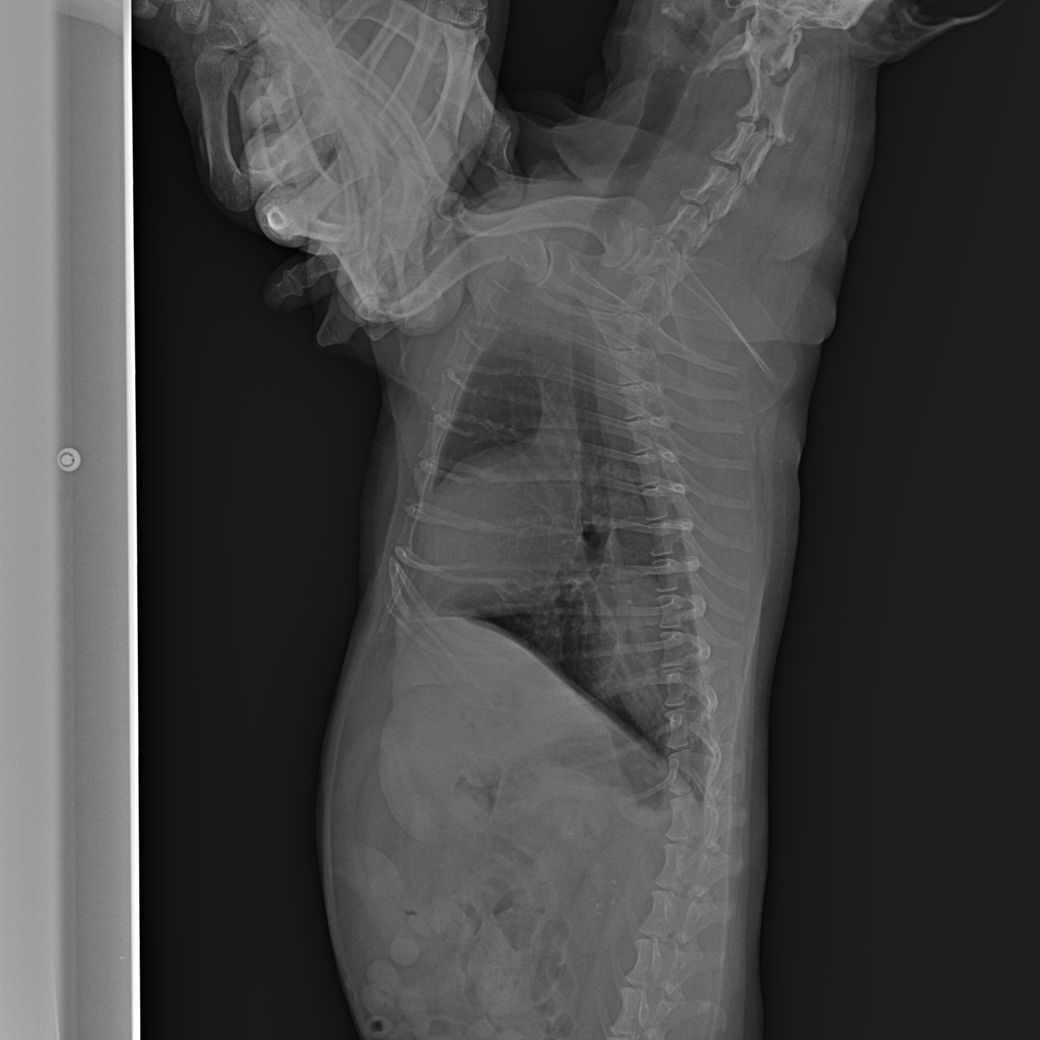

강아지가 식욕 저하와 기침을 많이 하고 거품 토를 해서 진료를 봤습니다. 헥헥거리는 증상도 있었습니다.

약을 처방받고 기침은 많이 줄었는데 방사선상으로 폐부분이 하얗게 보입니다.

2. 폐가 하얗게 보이는데 가능성은 높은 질병은 무엇일까요? CT가 정확하겠지만 상황이 되지 않아 문의드립니다.

또한 폐쪽도 강아지가 긴장하고 통증을 호소하게 되는 경우 호흡이 빠르므로 호기시 촬영한다면 폐가 뿌옇게 보일 수도 있습니다.

폐 후엽 의 내측면에 종괴성 병변이 관찰되며 원발성 폐종양의 호발 부위로

1. 이부분의 압박으로 식도가 눌리기 때문에 음식물을 먹을때 통증을 호소할 수 있고

2. CT를 찍어 확인할 필요가 있으나, 원발성폐종양, 식도종양, 폐농양, 식도게실, 육아종성병변 등을 고려해야합니다. 이는 CT로 어느정도 감별가능합니다

폐종양의 특징은 말기직전까지 "기침은 거의 하지 않습니다. 호흡도 괜찮습니다."라는 보호자의 병력이 특징적입니다. CT촬영 하시기 바랍니다.